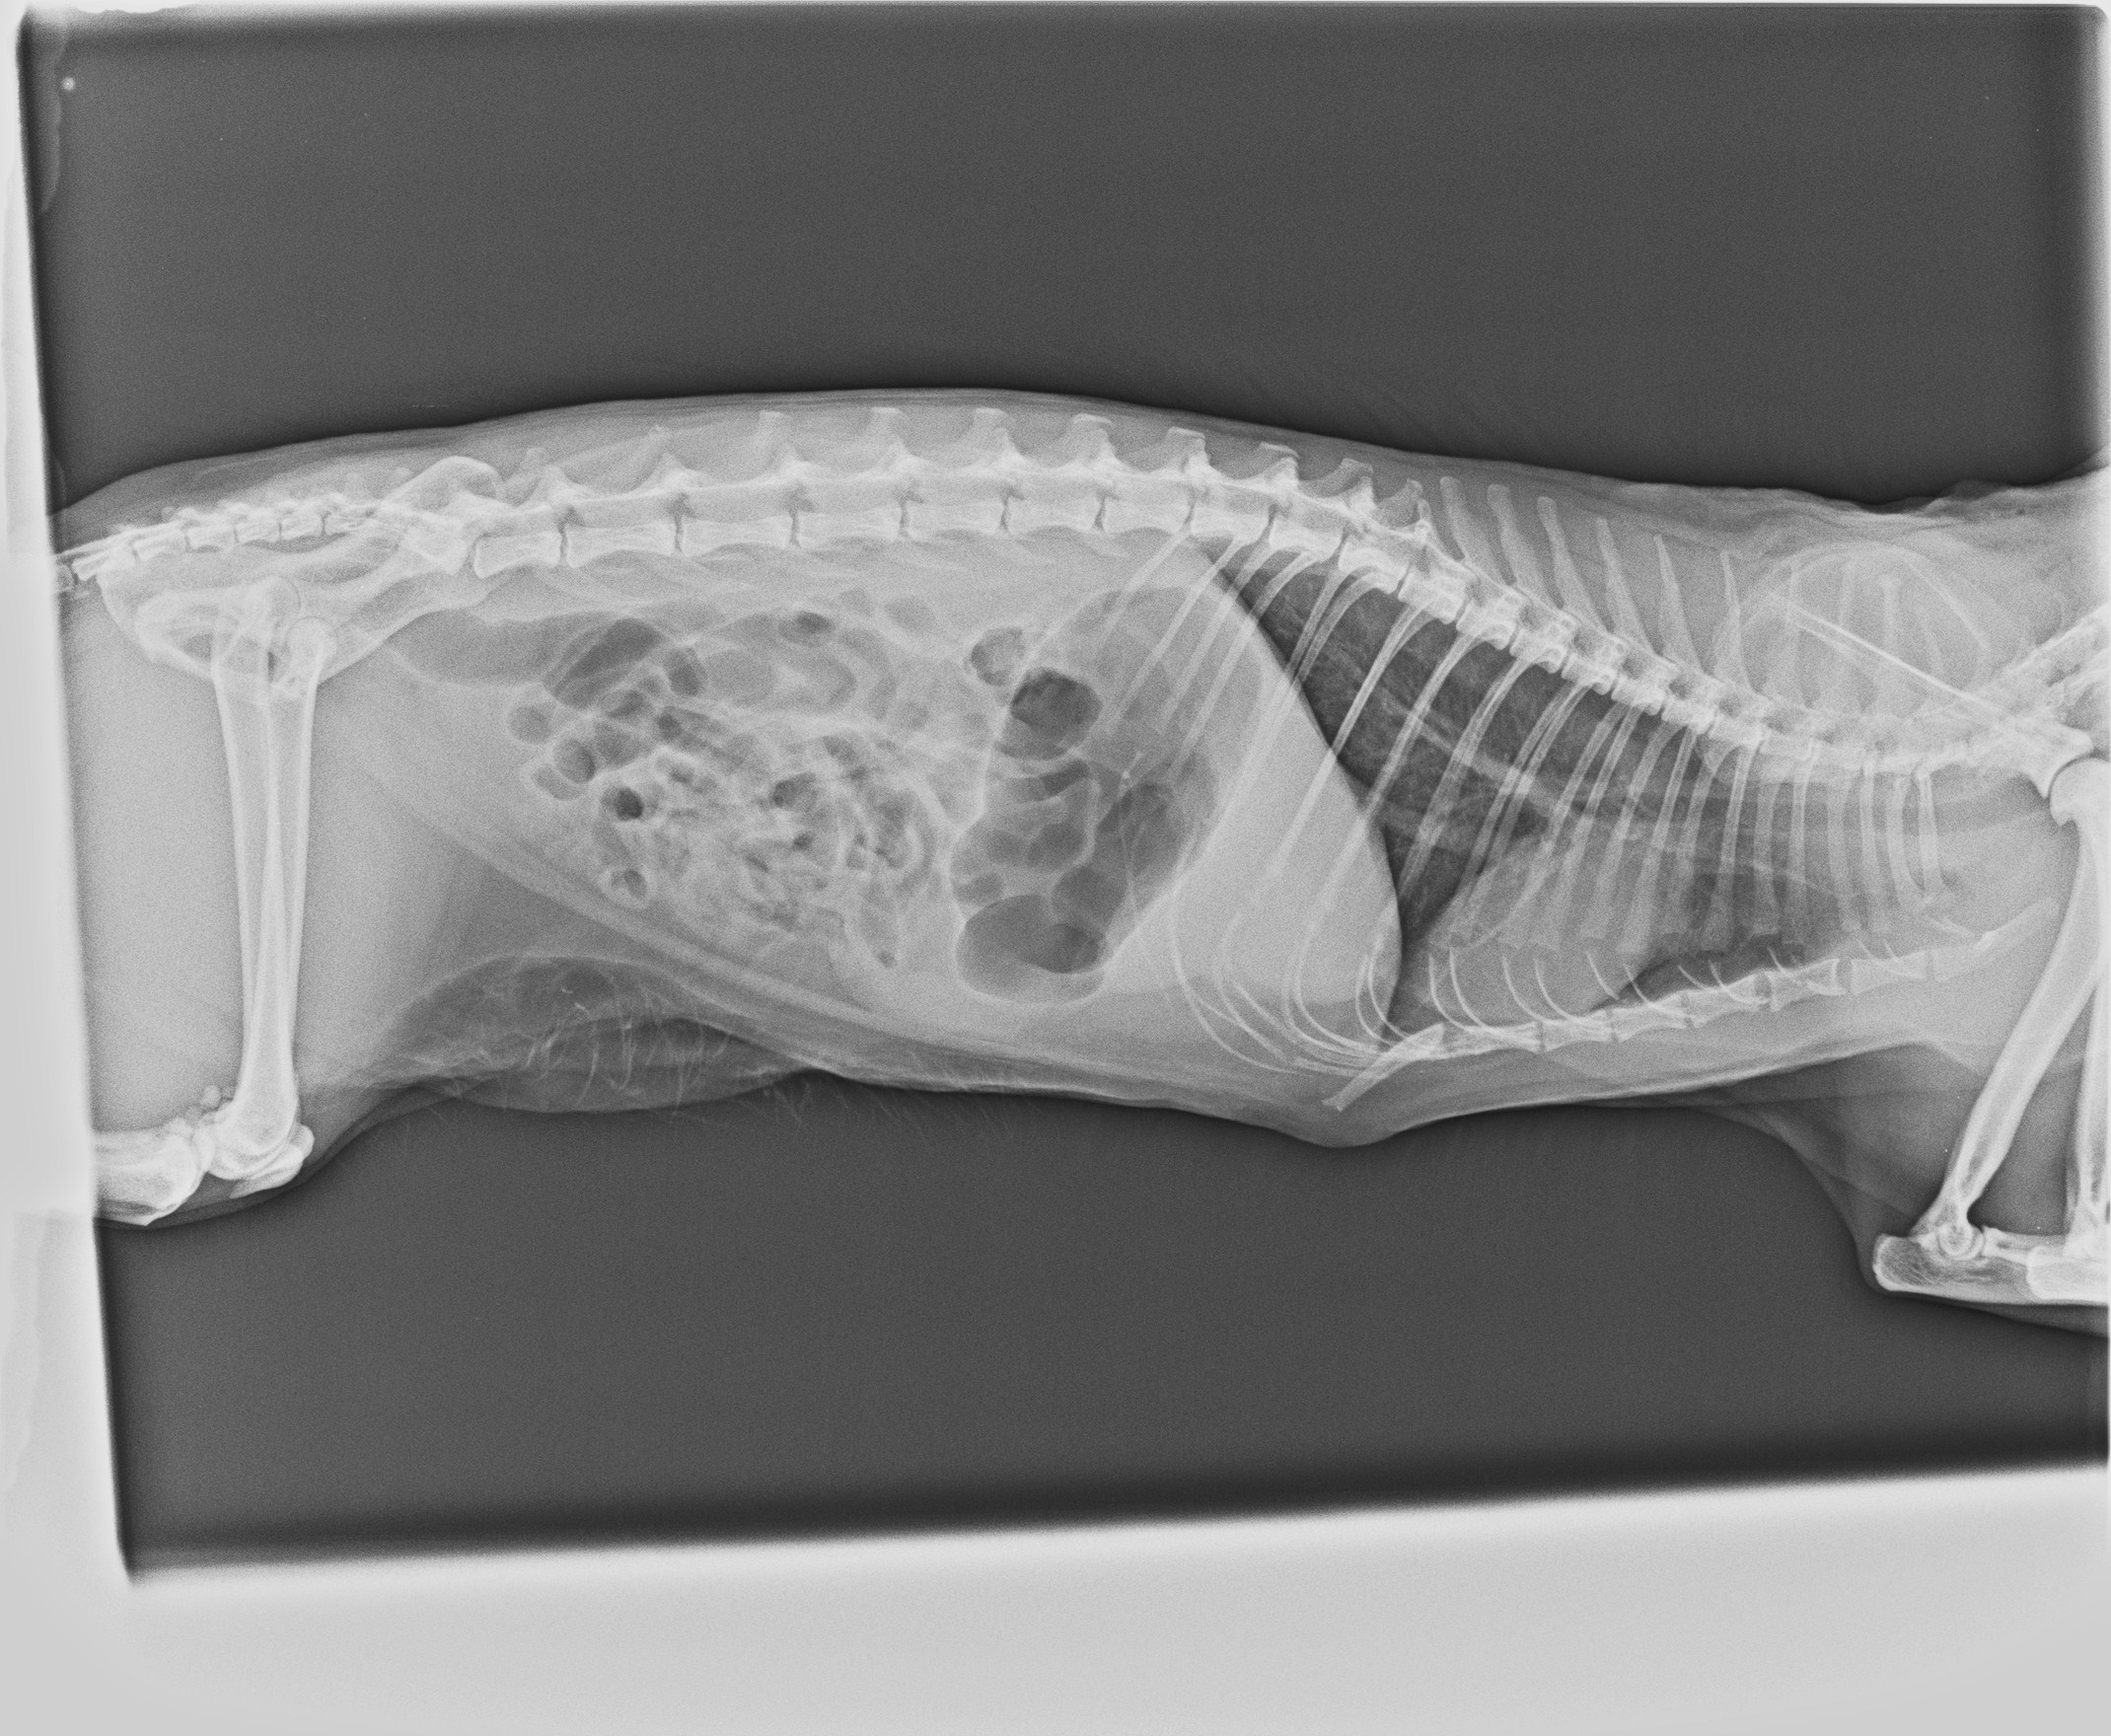

בוצע צילום רנטגן במנח ליטרלי (Letral View)

צילום רטגן ליטרלי letral xray view - בננה

ניתן להתרשם בצילום ההדמייה:

• מעיים: ניתן לראות בולטות של לולאות מעיים רבות שמכילות כמות גדולה של גז (האוויר השחור בצילום).

• קיבה: לא רואים הרחבה חריגה של הקיבה עצמה, יש אזורים של גז, ייתכן בקיבה ובמעי הדק. אין הרחבה של הקיבה.

• כבד: ככל הנראה, לא מוגדל משמעותית ולא חורג מגבולות כלוב הצלעות

• שלד: חוליות עמוד השדרה, אגן, וגפיים נראים ללא שברים או סטיות בולטים.

• בית החזה: לב וריאות

• אין סימני גודש ריאתי חריג.

• הצללה קלה באזור הלב, בגדר הנורמה לחתול במנח כזה.